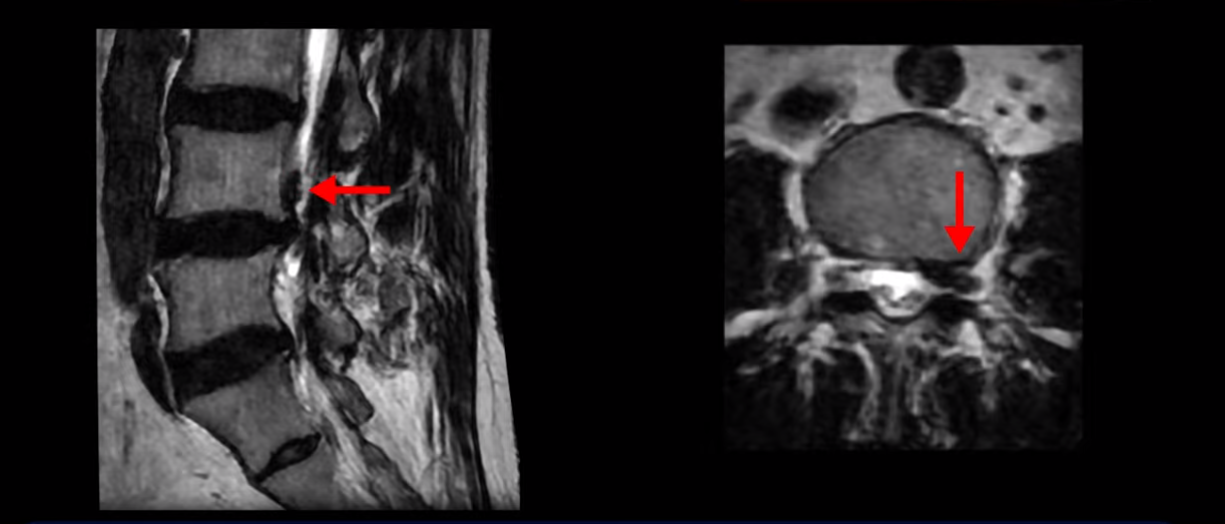

20251020_4

옆에서도 보이지만 단면에서도 왼쪽으로 심하게 밀려나온 수핵이 잘 보입니다.

20251020_5